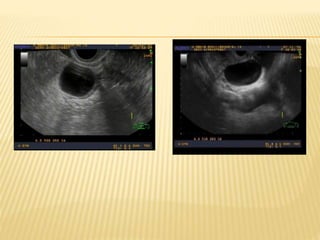

 Son uniloculares anecogénicos con paredes

finas bien definidas y refuerzo acústico

posterior

QUISTE HEMORRAGICO

 La hemorragia interna puede ocurrir en ambos quistes

funcionales

 Presentan dolor pélvico agudo

 El aspecto ecográfico depende de la cantidad de

hemorragia y del tiempo de la hemorragia en relación al

tiempo de la exploración ecográfica

 Un quiste hemorrágico agudo normalmente es

hiperecogénico y puede simular una masa sólida pero

presenta pared lisa y refuerzo posterior

 En la hemolización del coagulo el patrón interno se torna

complejo, con un patrón reticular que contiene septos y

ecos internos